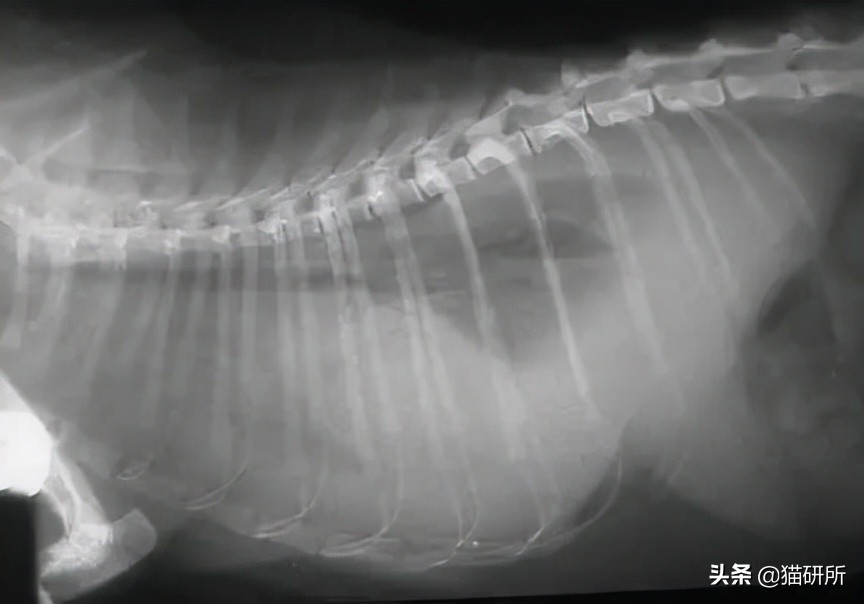

▍ B超/X 光 :传腹猫咪胸(腹)腔可能存在积液,器官形态出现异常,出现淋巴结肿大等

上图:正常猫咪的X光,能看见心肺等器官;下图:一片模糊,因为全是液体,看不见器官。图自:lbah

很多其他的疾病也可能导致猫咪出现腹水。 但对于青年猫(2岁以下)而言,出现腹水最常见的原因就是猫传腹。 (《猫病学(第5版)》)